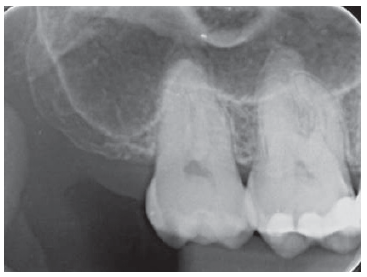

No que se refere à imagem radiográfica a seguir é correto afirmar que